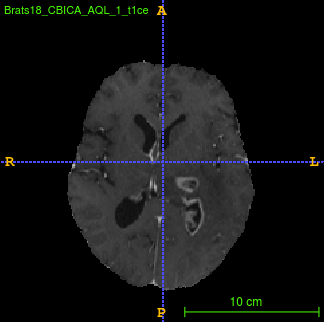

Segmentation of brain tumor from magnetic resonance imaging (MRI) is a vital process to improve diagnosis, treatment planning and to study the difference between subjects with tumor and healthy subjects. In this paper, we exploit a convolutional neural network (CNN) with hypercolumn technique to segment tumor from healthy brain tissue. Hypercolumn is the concatenation of a set of vectors which form by extracting convolutional features from multiple layers. Proposed model integrates batch normalization (BN) approach with hypercolumn. BN layers help to alleviate the internal covariate shift during stochastic gradient descent (SGD) training by zero-mean and unit variance of each mini-batch. Survival Prediction is done by first extracting features(Geometric, Fractal, and Histogram) from the segmented brain tumor data. Then, the number of days of overall survival is predicted by implementing regression on the extracted features using an artificial neural network (ANN). Our model achieves a mean dice score of 89.78%, 82.53% and 76.54% for the whole tumor, tumor core and enhancing tumor respectively in segmentation task and 67.90% in overall survival prediction task with the validation set of BraTS 2018 challenge. It obtains a mean dice accuracy of 87.315%, 77.04% and 70.22% for the whole tumor, tumor core and enhancing tumor respectively in the segmentation task and a 46.80% in overall survival prediction task in the BraTS 2018 test data set.